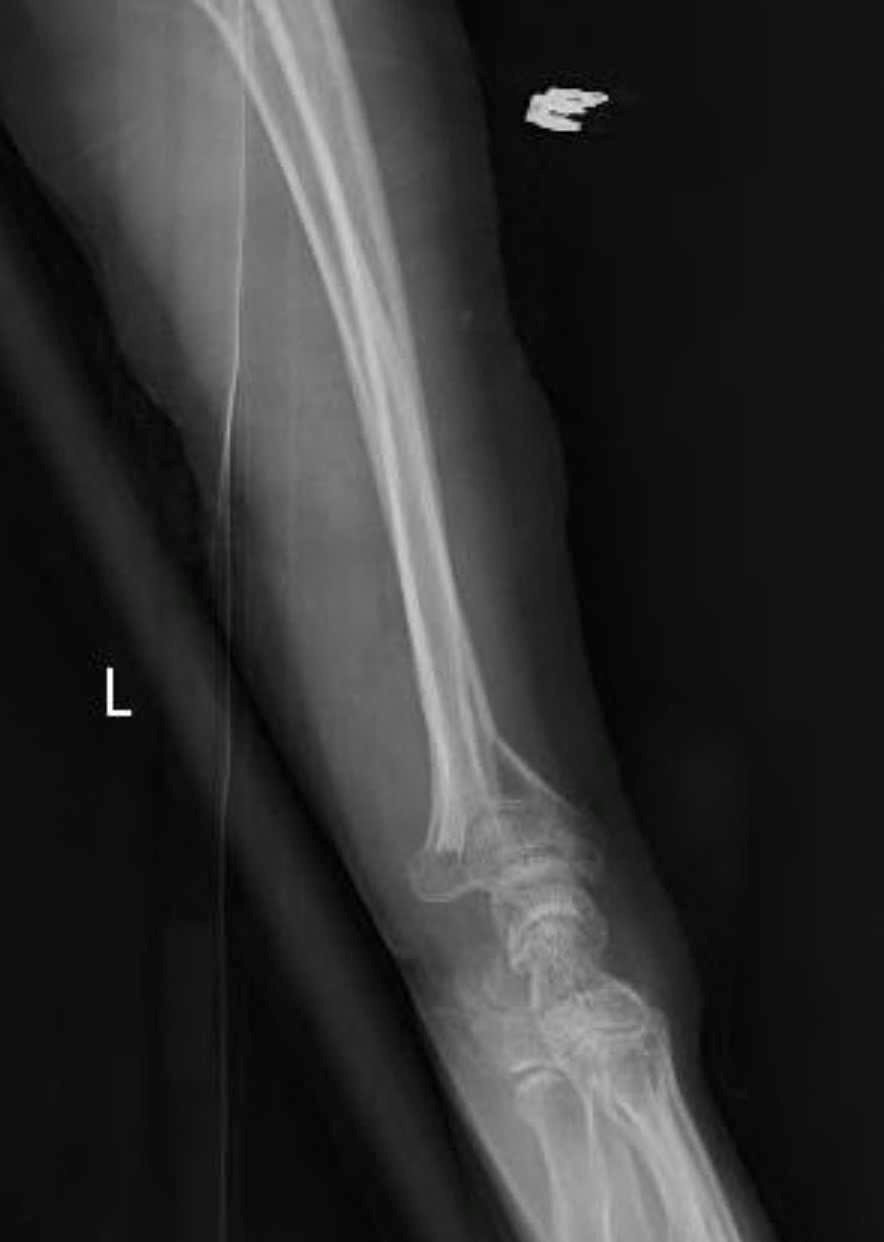

Bs.CKII Phạm Đình Thành - Phó Giám đốc Trung tâm CTCH - Bỏng (thuộc BVĐK Khánh Hoà) cho biết, đoàn chuyên gia đã phối hợp cùng các bác sĩ của Trung tâm tiến hành phẫu thuật thành công cho một bệnh nhân đa chấn thương nghiêm trọng. Đây là nạn nhân trong vụ tai nạn lật xe xảy ra vào ngày 10/4/2026 tại đèo Hòn Bà. Bệnh nhân nhập viện trong tình trạng gãy nhiều xương phức tạp, cụ thể là gãy nát lồi cầu đùi và gãy nát đầu dưới xương quay hai bên. Nhờ sự can thiệp kịp thời và trình độ chuyên môn cao của ê-kíp phối hợp, ca phẫu thuật đã diễn ra tốt đẹp.